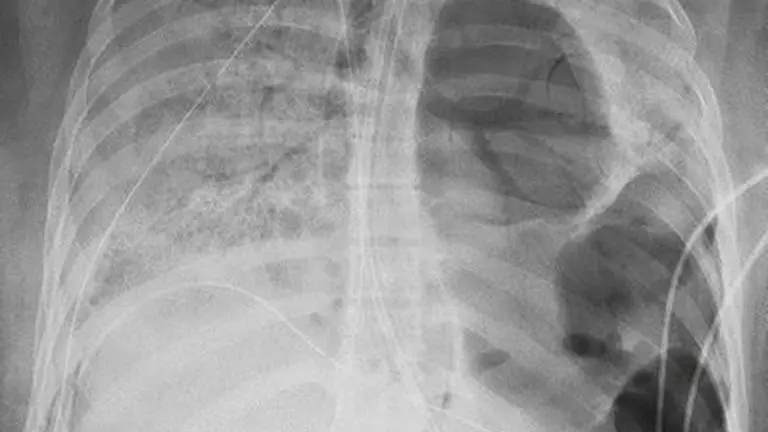

A young paralegal and a car mechanic received lifesaving double lung transplants in Chicago after COVID-19 destroyed their lungs.

Doctors at Northwestern Medicine in Chicago say COVID-19 caused severe lung failure in the patients, making transplant surgery their only option.